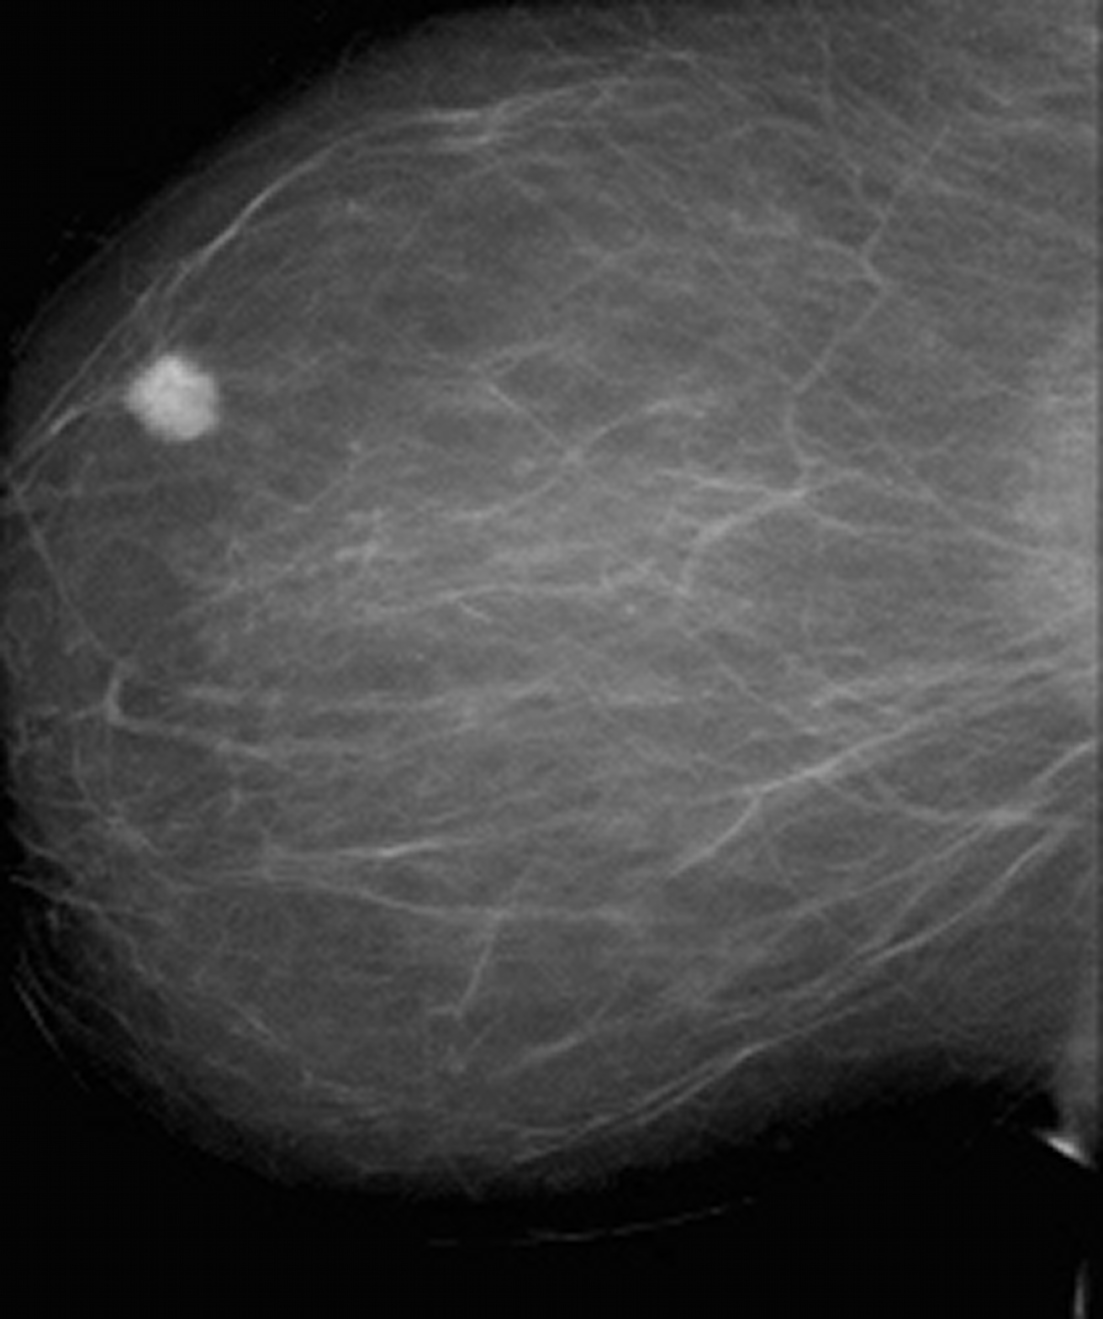

Фиброаденома молочной железы - доброкачественное образование, которое часто встречается у женщин. Оно может быть обнаружено при помощи различных методов диагностики, включая маммографию. Ниже представлены фотографии, помогающие понять, как выглядит данное заболевание.

Маммография и ее роль в диагностике фиброаденомы молочной железы

Маммография - это рентгенологическое исследование молочных желез. Оно позволяет выявить различные изменения в тканях, включая фиброаденому. На маммограммах можно увидеть структурные особенности опухоли и отследить ее динамику во времени.